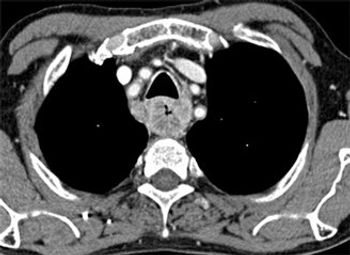

Developing a scoring system for staging patients with hepatic colorectal metastases is important for prognosis and for identifying those who will benefit from additional systemic therapy.

Due to advances in chemotherapy, biologic therapy, and the development of liver-oriented treatment options, the survival of patients with metastatic cancer has more than doubled, and increasing numbers of patients have been cured, even among those with advanced disease.

This article will review the current practice of hepatic resection for colorectal liver metastases, including the possibility of combined resection of hepatic metastases at the time of resection of the primary cancer.